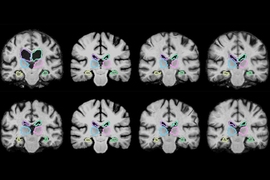

Caption: MIT researchers have developed a system that gleans far more labeled training data from unlabeled data, which could help machine-learning models better detect structural patterns in brain scans associated with neurological diseases. The system learns structural and appearance variations in unlabeled scans, and uses that information to shape and mold one labeled scan into thousands of new, distinct labeled scans.

MIT researchers have developed a system that gleans far more labeled training data from unlabeled data, which could help machine-learning models better detect structural patterns in brain scans associated with neurological diseases. The system learns structural and appearance variations in unlabeled scans, and uses that information to shape and mold one labeled scan into thousands of new, distinct labeled scans.